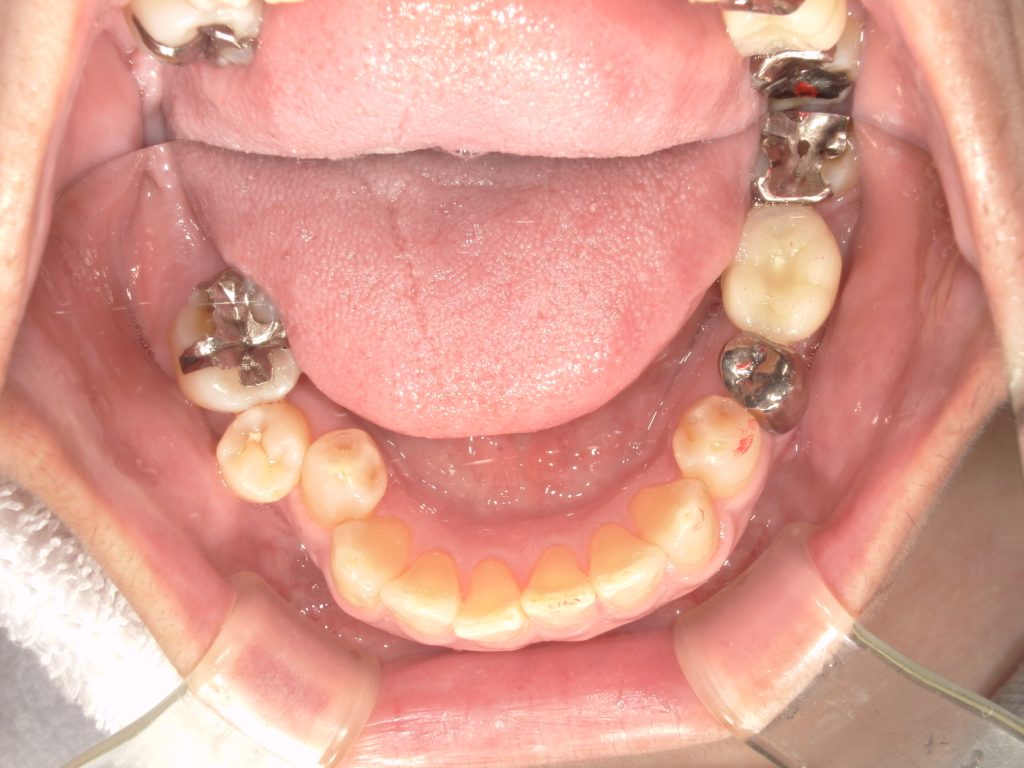

Y様インプラント実例 #44

左の上下の奥歯をインプラントで治療しています。

左下の奥歯は歯を抜くのと同時にインプラントの埋め込みを行っています。

被せものは上下、セラミックスで作っています。

治療前

治療後